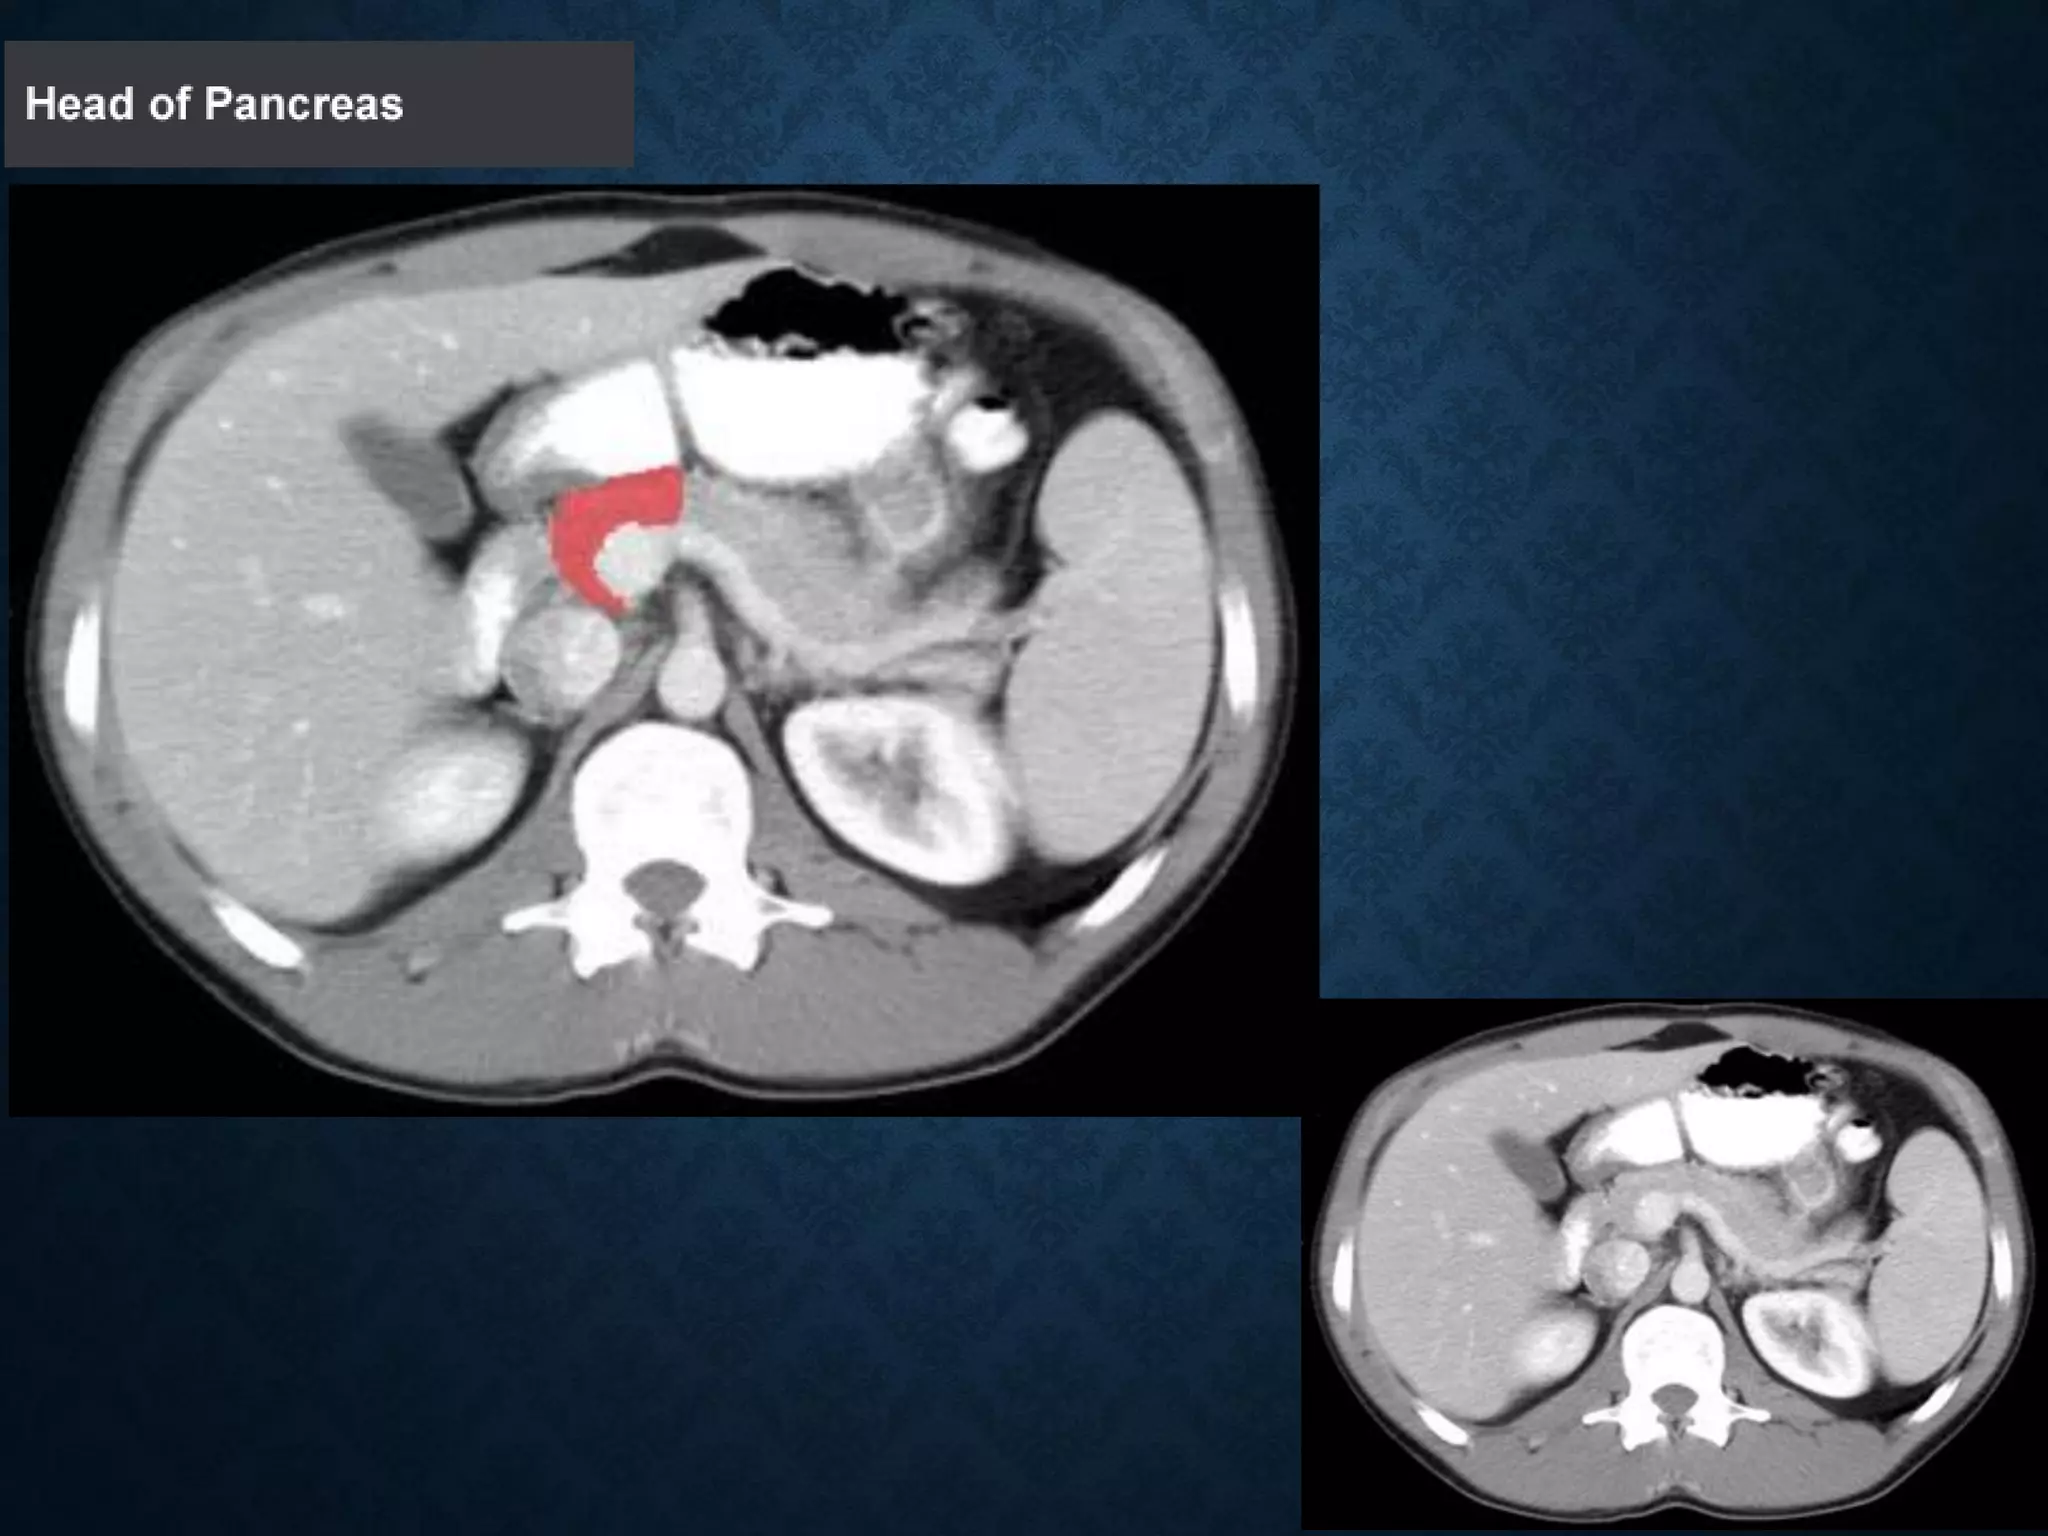

1: Head of pancreas

PANCREAS 1: Head ofpancreas 2: Uncinate process of pancreas 3: Pancreatic notch 4: Body of pancreas 5: Anterior surface of pancreas 6: Inferior surface of pancreas 7: Superior margin of pancreas 8: Anterior margin of pancreas 9: Inferior margin of pancreas 10: Omental tuber 11:Tail of pancreas 12: Duodenum

1: Head ofpancreas 2: Uncinate process of pancreas 3: Pancreatic notch 4: Body of pancreas 5: Anterior surface of pancreas 6: Inferior surface of pancreas 7: Superior margin of pancreas 8: Anterior margin of pancreas 9: Inferior margin of pancreas 10: Omental tuber 11:Tail of pancreas 12: Duodenum